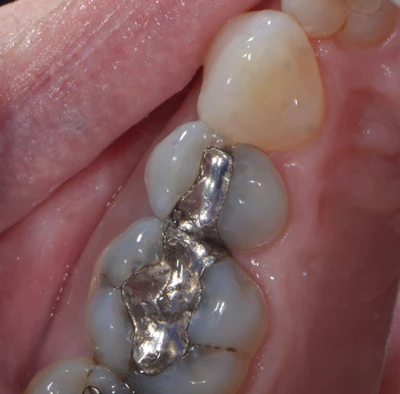

Sixteen Catapult education evaluators participated in the survey, where Visalys Bulk Flow was used in class I, class V preparations, and as a liner and in limited anterior cases. Bulk flowable composites are not generally favored in the aesthetic zone, thus the limited testing in that area. Evaluators noted the balance Visalys Bulk Flow achieved between flowability and stability. Many bulk-flow materials have a very high viscosity, leading to a runny consistency or prone to slumping, but Visalys Bulk Flow held its shape while still adapting well to the preparation. Several evaluators described it as easy to sculpt and particularly useful, especially in small occlusal preparations and cervical lesions (Figures 1, 2).

Figure 2: Immediate post-op, after placement in class I restorations on both lower premolars.